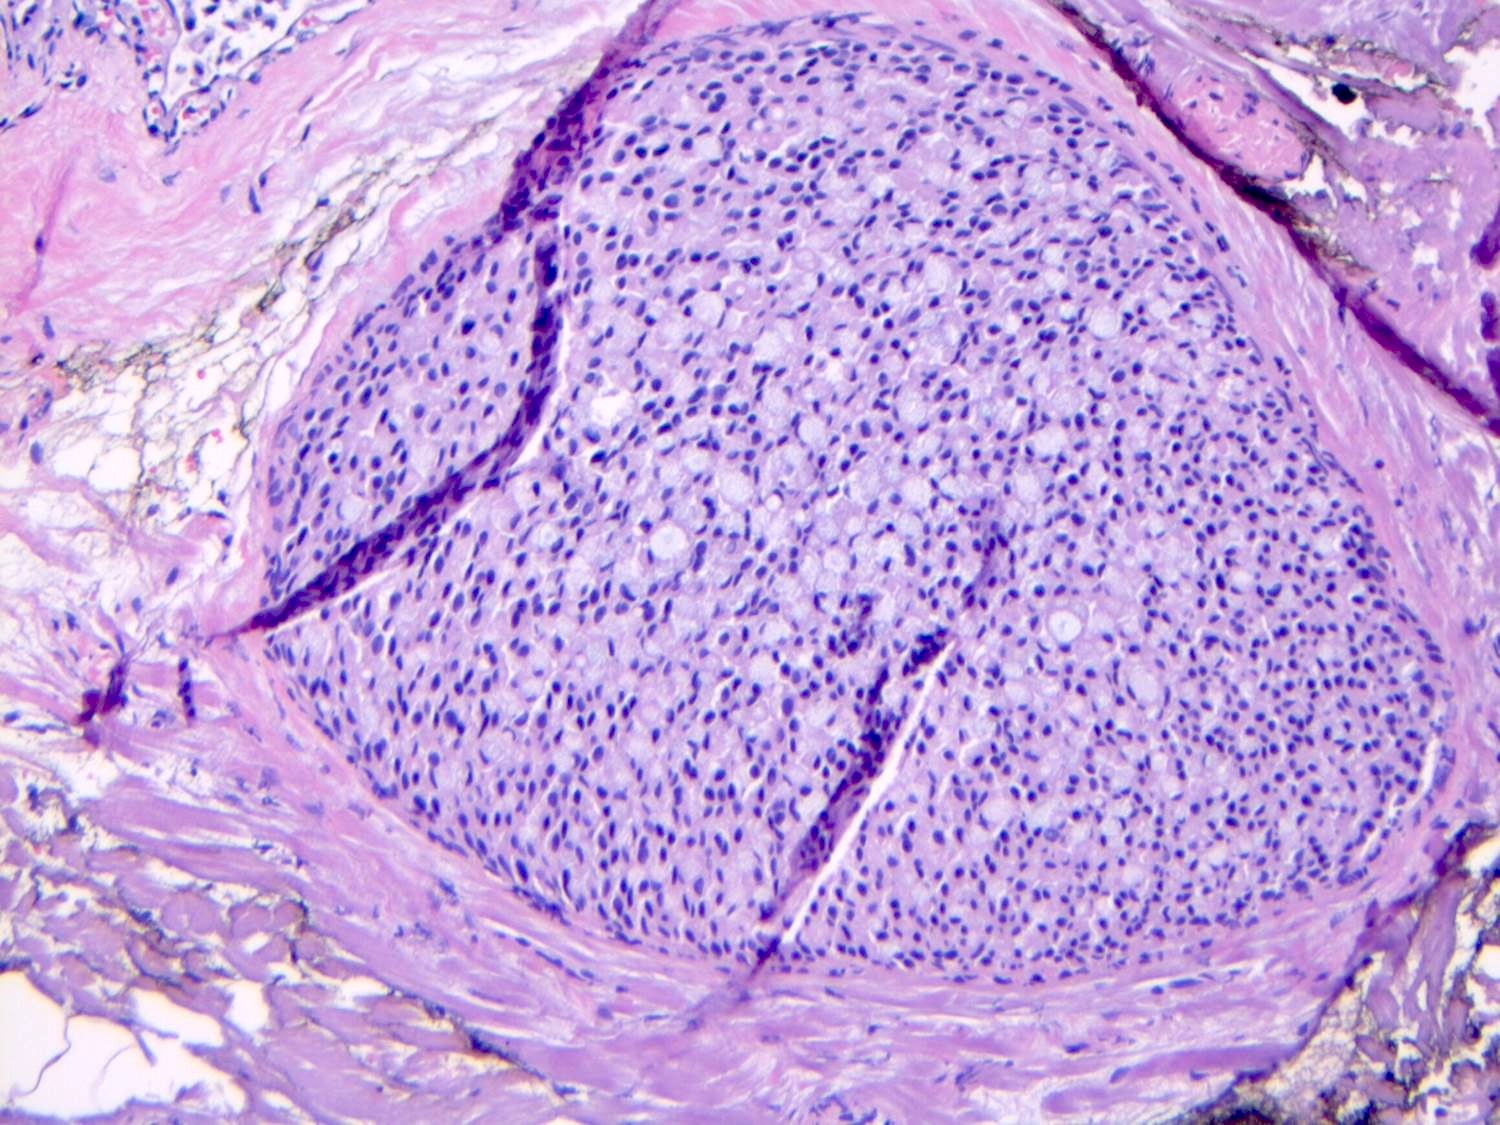

Microscopic (histologic) description

- LCIS involves the terminal duct lobular unit (TDLU), filling and distending acini

- > 50% of the acini in a TDLU must be filled and expanded to qualify as LCIS; otherwise, called atypical lobular neoplasia

- Lobular distention is defined as the presence of ≥ 8 cells in the cross sectional diameter of an acinus

- Involved lobules may be compared with uninvolved lobules to estimate the degree of distension

- LCIS most often involves lobules but may also grow along the basement membrane of ducts (i.e., pagetoid spread)

- Pagetoid spread in ducts is the characteristic growth of cells between luminal and myoepithelial layers of a duct without destroying ductal epithelium or filling up ductal lumina

- Often makes the ducts appear convoluted; this is called a cloverleaf pattern

- Classic LCIS cells are monomorphic, evenly spaced, loosely cohesive and do not show polarization or gland formation

Microscopic (histologic) images

Contributed by Anna Biernacka, M.D., Ph.D.